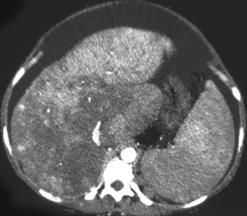

Budd-Chiari Syndrome